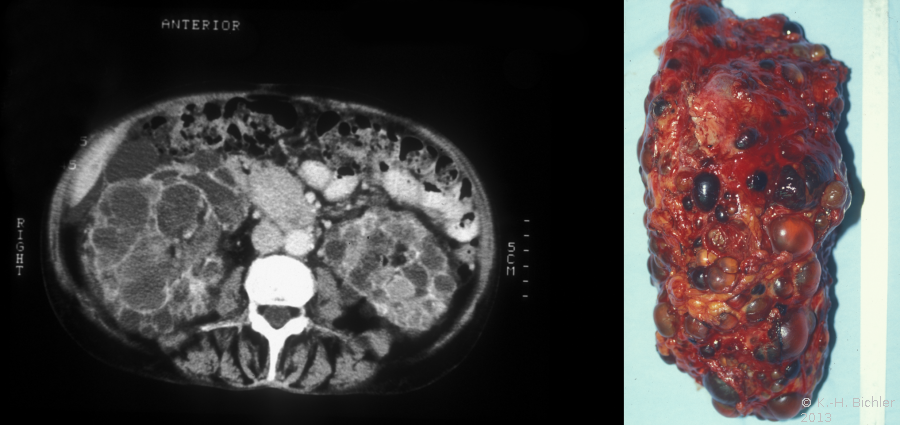

Die Diagnose wird mittels Anamnese (zystische Nierenerkrankungen in der Familie), RR-Messung, Labor (Kreatinin) mit genetischer Untersuchung, Sonographie, Computertomographie und gegebenfalls Kernspintomographie gestellt (Abbildung 4).